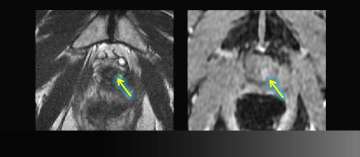

8) Benign Disease (Infertility)

- Young man presents with infertility (azospermia)

- Workup and medical history otherwise noncontributory

- Muellerian duct remnant in central upper prostate may obstruct ejaculatory ducts

- Left seminal vesicles are atrophic